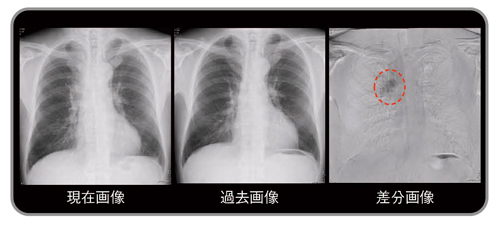

既存肺構造である肺門・縦隔や横隔膜陰影に重なって病変としてとらえ難い病変や,境界が不整だったり不鮮明な病変でも,差分画像では鮮明に結節が描出されている(図4〜6)。

図6 有用症例:左肺門部に重なる陰影(扁平上皮癌)